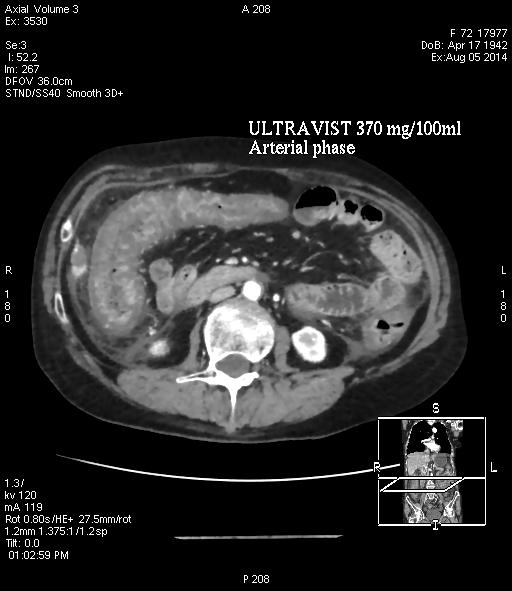

Кт слепой кишки

Кт слепой кишки 112 фото